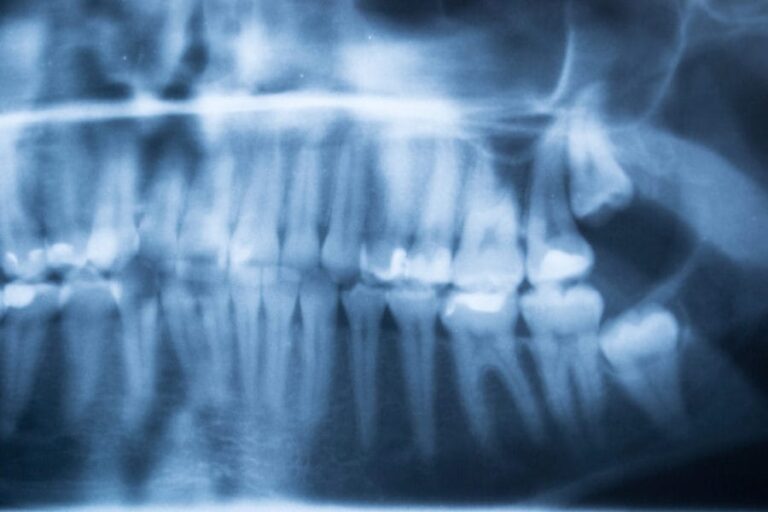

There are 4 Different Types of Wisdom Teeth Removals:

- No Impaction: The wisdom tooth is showing above jawbone and gums.

- Soft Tissue Impaction: The gums cover the teeth. Sometimes your dentist needs to cut a flap into the gum to expose the wisdom tooth for extraction.

- Partial Bony Impaction: Part of the wisdom tooth’s crown is trapped in the jawbone. Your dentist must cut away the gum and remove a small amount of the jawbone to extract the tooth. The wisdom tooth may need to be sectioned (cut) for removal.

- Complete Bony Impaction: the tooth is surrounded by a jawbone that needs to be removed to expose the wisdom tooth for extraction.